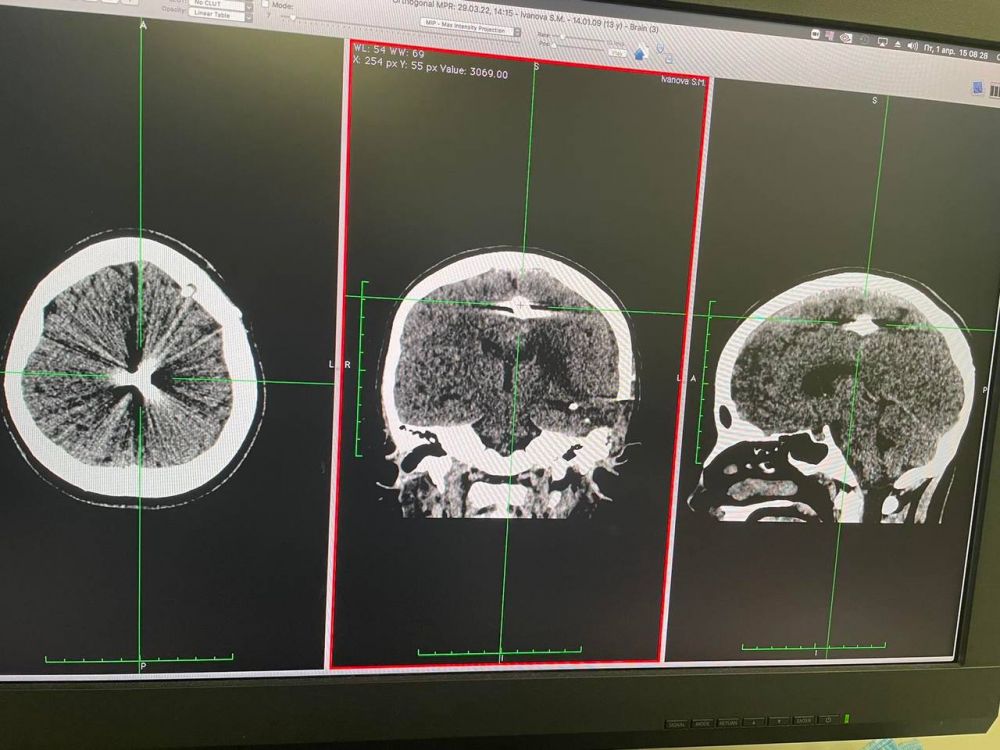

29 березня лікарі дитячої лікарні «Охматдит» прооперували 13-річну Софію. З її голови медики дістали уламок снаряду, який пройшов через скроню та зупинився між півкулями головного мозку.